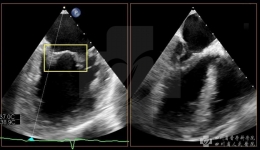

我院成功开展首例心脏收缩力调节器植入手术

4月11日,我院心血管内科心脏电子器械植入(CIED)团队为一位患有扩心病的男性患者成功植入心脏收缩力调节器(CCM)。该术式的成功开展,使我院慢性心衰患者的器械治疗手段更加全面。患者为59岁中年男性,两年来反复出现心累、气促,诊断为扩张型心...